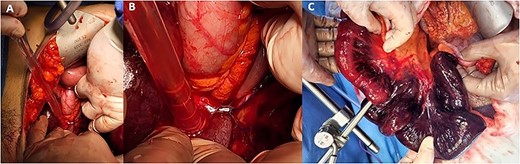

A direct trocar entry from the Jain point enabled visualization of the intraabdominal contents, demonstrating haemoserous fluid and extensive lengths of ischaemic bowel. The operation was converted to an open laparotomy via a midline incision. Upon inspection of the bowel, it was evident that a recently placed V-Loc suture had been mistakenly placed through the bowel anchoring it in the pelvis and providing a point for volvulus to occur, resulting in ischaemic bowel (Fig. 2). Upon removal of the suture, the bowel was able to be mobilized. 1.2 metres of ischaemic terminal ileum was resected, and a side-to-side anastomosis fashioned with a GIA −80 stapler.

Intraoperative ischaemic bowel. (A) Identification of the transition point for the ischaemic bowel and suture in the left iliac fossa. (B) The suture placed during previous robotic surgery transecting the bowel and resulting in a volvulus. (C) 1.2 metres of ischaemic terminal ileum.

We report a novel complication of malplacement of a V-Loc suture during RALSC resulting in a closed loop bowel obstruction (Fig. 1) and resultant ischaemic bowel (Fig. 2). Whilst barbed, absorbable sutures are widely utilized as they reduce suturing time and technical difficulty [6] they also carry a risk of bowel obstruction of 1/400 [7]. Most describe the adverse event occurring because of the entanglement of barbed wire tails between the intestinal mesentery or epiploic appendages [8]. With the lack of haptic feedback in robotic surgery, it is possible for surgeons to place a suture deeper than expected, which we hypothesize happened in this case.